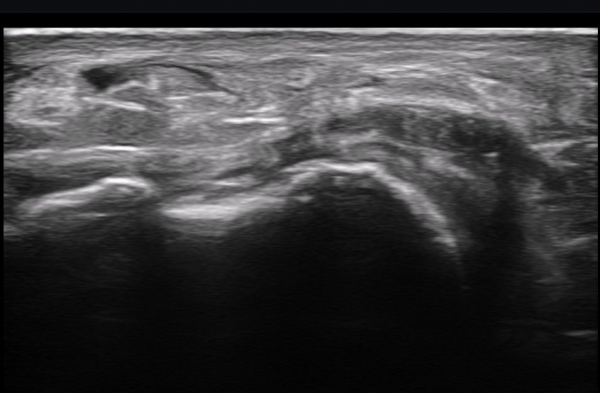

ÃÊÀ½ÆÄ ¼Ò°ß : ºñº¹½Å°æ Ⱦ´Ü¸é°Ë»ç¿¡¼­(»çÁø 1~13) ºñº¹½Å°æÀÇ Àú¿¡ÄÚ ºÎÁ¾°ú ´Üºñ°ñ°Ç³» ³¶Á¾¼º º´º¯ÀÌ °üÂûµÈ´Ù.